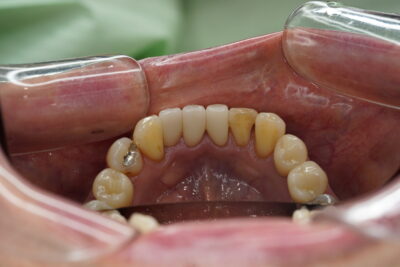

こちらが処置前Photoになります

右下中切歯にメタルとその両隣の歯に虫歯が、また並びが重なっていてそこも気になる!とのことで治療することとなりました